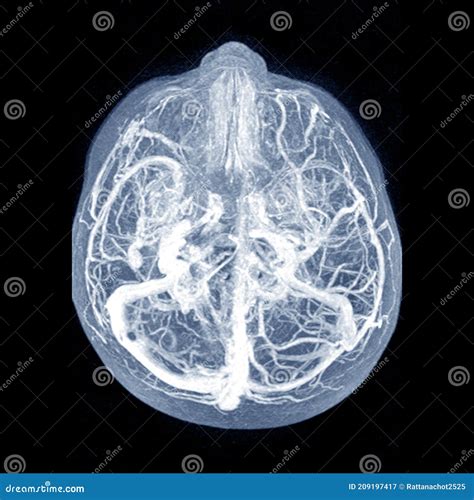

Understanding the complexities of the human brain is a fascinating journey that often leads to intriguing discoveries. One such phenomenon is the Midline Shift Brain, a condition that has garnered significant attention in the fields of neurology and psychology. This condition, characterized by a shift in the midline structures of the brain, can have profound effects on an individual's cognitive and motor functions. In this post, we will delve into the intricacies of the Midline Shift Brain, exploring its causes, symptoms, diagnostic methods, and potential treatments.

The brain is a complex organ with various structures that work together to control different functions of the body. The midline structures, which include the corpus callosum, thalamus, and hypothalamus, play crucial roles in coordinating these functions. A Midline Shift Brain occurs when these structures are displaced from their normal positions, often due to trauma, tumors, or other pathological conditions.

• Imaging Studies: Imaging techniques such as CT scans and MRI are crucial for visualizing the brain and detecting any shifts in the midline structures. These tests provide detailed images that can help identify the cause and extent of the midline shift.